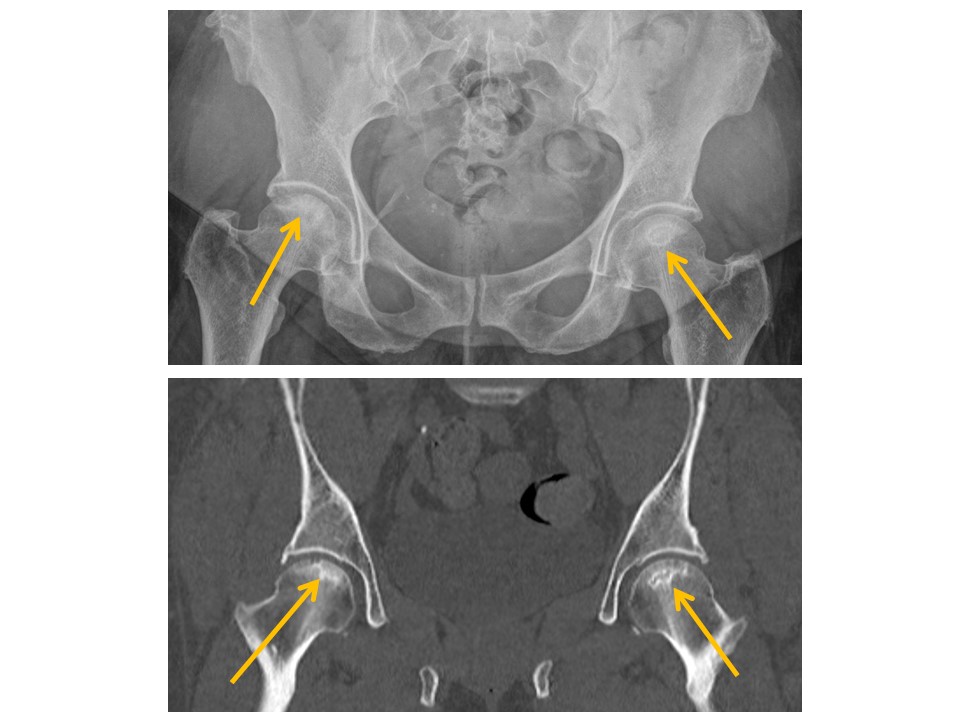

HIPS/PROXIMAL FEMURS

There is osseous prominence at the lateral femoral head/neck junctions. [Yes/No]

There are fractures of the femoral neck, intertrochanteric region, or subtrochanteric region. [Yes/No]

There are avulsion fractures of the greater or lesser trochanters.

[Yes/No]